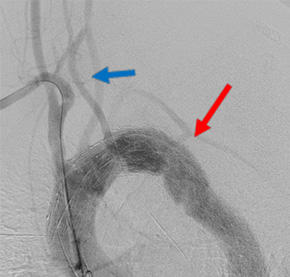

胸部大動脈瘤におけるハイブリッド治療

頸動脈と鎖骨下動脈をバイパス(青矢印)・開窓型ステントグラフトで瘤を空置(赤矢印)